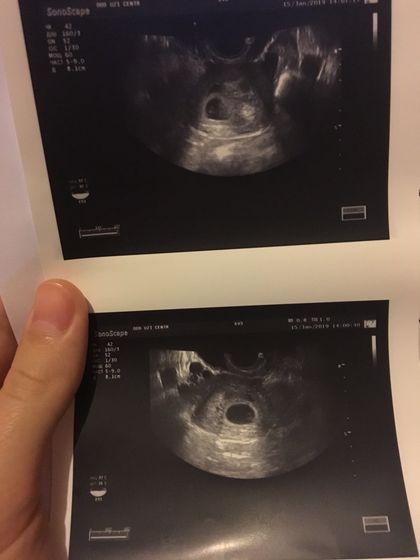

Сегодня ходила на узи, сказала все хорошо и в понедельник прийти на учёт вставать, эта врач узи ещё работает у нас в ЖК, сказала по прописке моя врач скоро сама в декрет уходит и по этому она сказала поможет мне встать к другому врачу на учёт. Все нам пророчат сынишку поголовно? Грудь ещё ужасно болит и видимо выросла уже на размер, сегодня покупала новый бюстгальтер по больше, из обычных уже вылазиют ??♀️ До сих пор не верится что скоро у нас будет чудо маленькое ?

Поздравляю!) А делали снаружи или внутри УЗИ?

Внутри

Сердцебиение услышали?

Увидели что пульсирует сердечко но ещё рано и не услышали